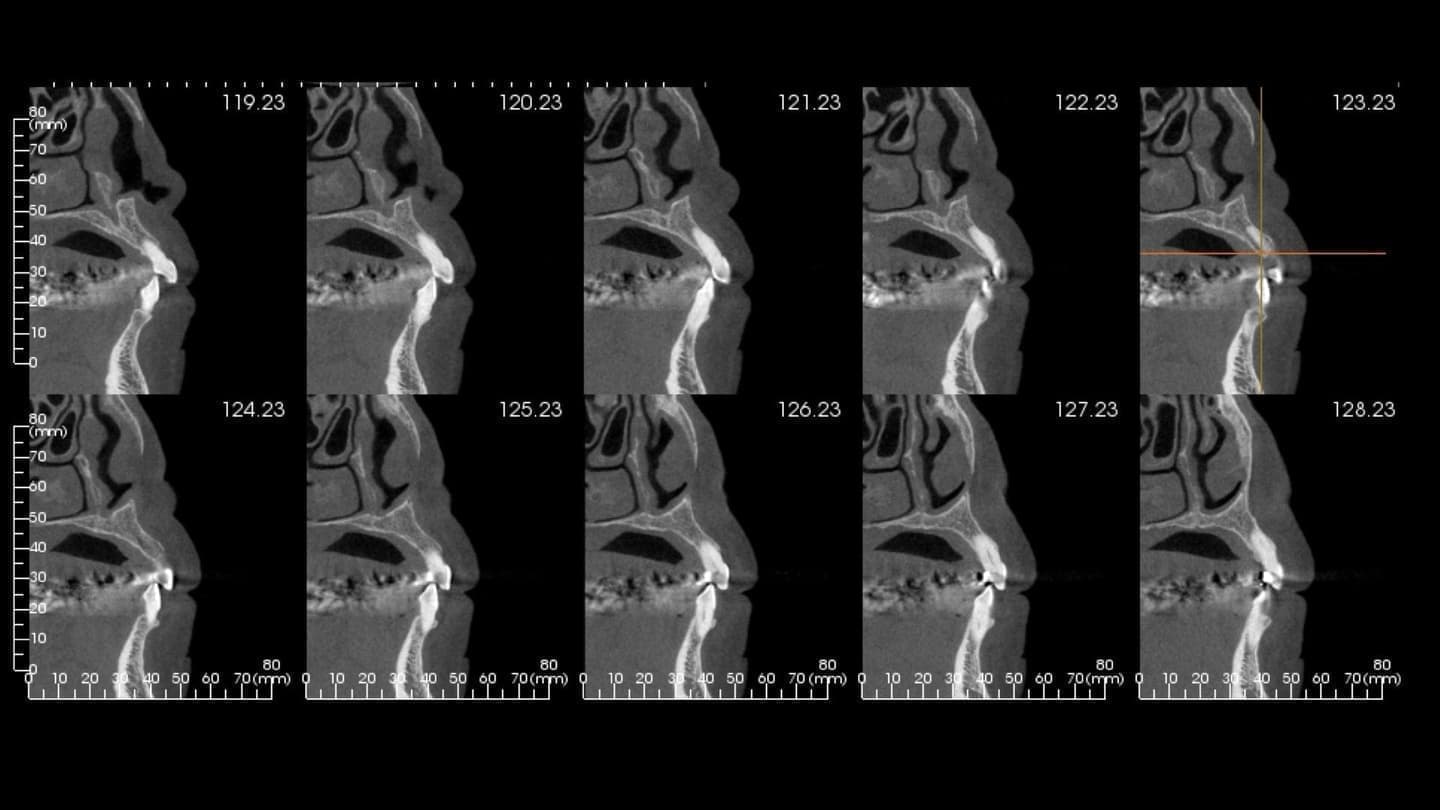

CT設備完備

二次元のレントゲン(歯科医院にある通常のレントゲン)では見えなかったこと、分からなかったことが、歯科用CTなら正確な診査と診断ができ、安全性と治療のクオリティーを高めることが可能となります。

インプラント手術においてCT撮影は必須です。CT撮影を行うか否かも医院を選ぶうえでの判断材料にしていただければと思います。